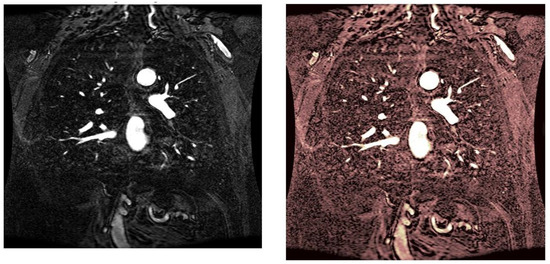

As statistical data have less relevance for life sciences, we add graphical displays of the studied angiograms. Surprisingly, even a simple denoising procedure can help reduce unwanted artifacts, as can be observed when comparing the angiogram E1154S7I064 (shown in Figure 5) with the result obtained by denoising it with the CLAHE method already described (shown in Figure 6). The corresponding image obtained by the wavelet-based CE method (shown in Figure 7) better outlines the biological features, making visible some details that cannot be observed in the original image (Figure 5), and allows us to take into consideration relinquishing contrast substances (a fact with multiple benefits for newborns and children). A visual comparison of CLAHE and wavelet-based CE method results in the performance obtained for this angiogram can be made with the images in Figure 8. It can be noticed that the original image is too dark to observe all the significant medical details and that the result of CLAHE is too luminous and can mask medical features. The same remarks concerning the advantages of the wavelet-based CE methods can be made upon a visual analysis of the original angiograms and the corresponding results shown in Figure 9, Figure 10, Figure 11 and Figure 12.

Figure 8. Different results to show the contrast improvements given by different CE algorithms. Left image: local contrast of the absolute value of the DT-CWT image corresponding to the angiogram E1154S7I064. Right images: zoom in the same region of the original image (up), result of wavelet-based CE method (middle), and result of CLAHE method (bottom).

Figure 9. Original angiogram E1154S7I001 (left) and wavelet-based CE method result (right).